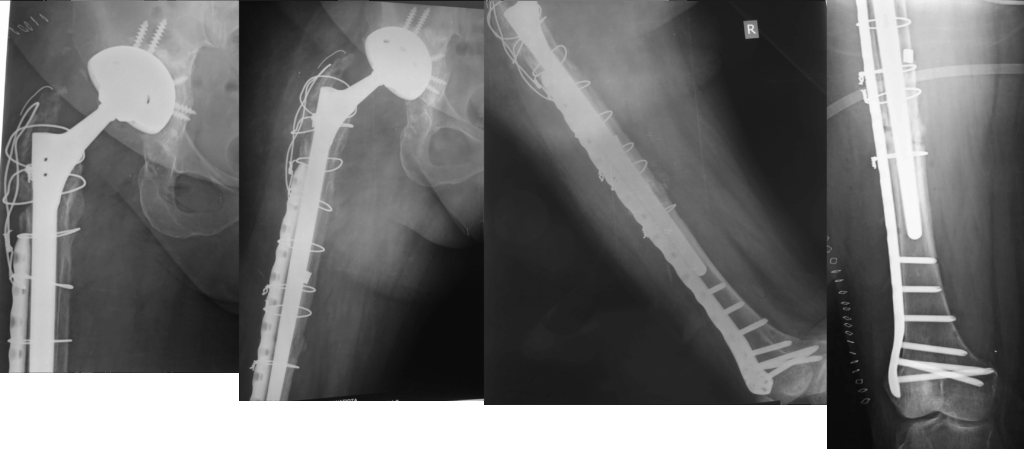

Κατάγματα γύρω από την πρόθεση

Ανακατασκευή του οστού (αν υπάρχει οστική απώλεια)

Τοποθέτηση νέας πρόθεσης, ειδικά σχεδιασμένης για αναθεωρήσεις

Οι προθέσεις αναθεώρησης είναι πιο σταθερές, μακρύτερες και συχνά συνδυάζονται με μοσχεύματα ή μεταλλικά ενθέματα.